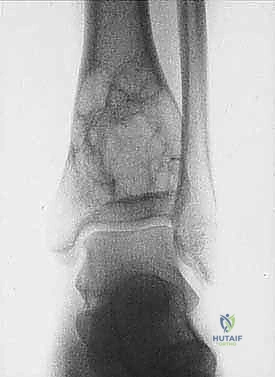

3. الكسور المرضية: حدوث كسر في العظم نتيجة إصابة طفيفة جداً لا تسبب كسراً في العظم السليم.

| حدود الورم في الأشعة | واضحة، محددة بدقة (Sclerotic margin) | غير واضحة، متآكلة (Moth-eaten appearance) |

| اختراق قشرة العظم | نادر جداً | شائع جداً، يمتد للأنسجة الرخوة المحيطة |

2. الموقع (Site - T): هل الورم داخل الحيز العظمي (Intracompartmental - T1) أم اخترق القشرة وخرج للحيز الخارجي (Extracompartmental - T2)؟